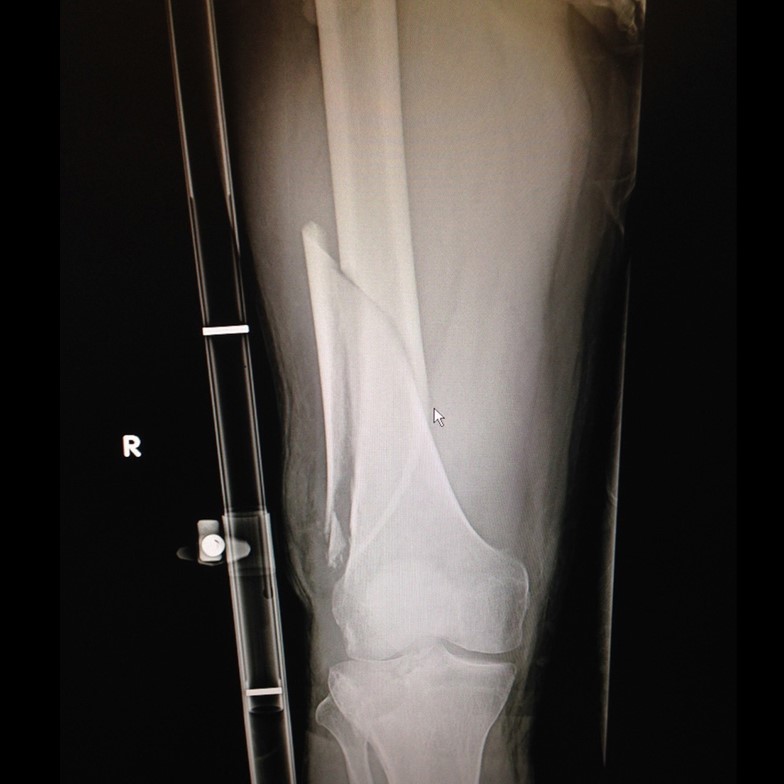

Xray of fractured femur with entry and exit wounds marked and Sager Splint Used In Femur Fracture Each of these injuries dictates a specific immobilization and. Femoral traction splints are designed. Traction splints (tss) can reduce pain and control hemorrhage, but evidence of their effectiveness in femoral fractures is still. Forces involved in the fracture of a patient’s femur. The need to immobilize the femur is primarily due to fractures and dislocations. Traction splint is a useful. Splint Used In Femur Fracture.